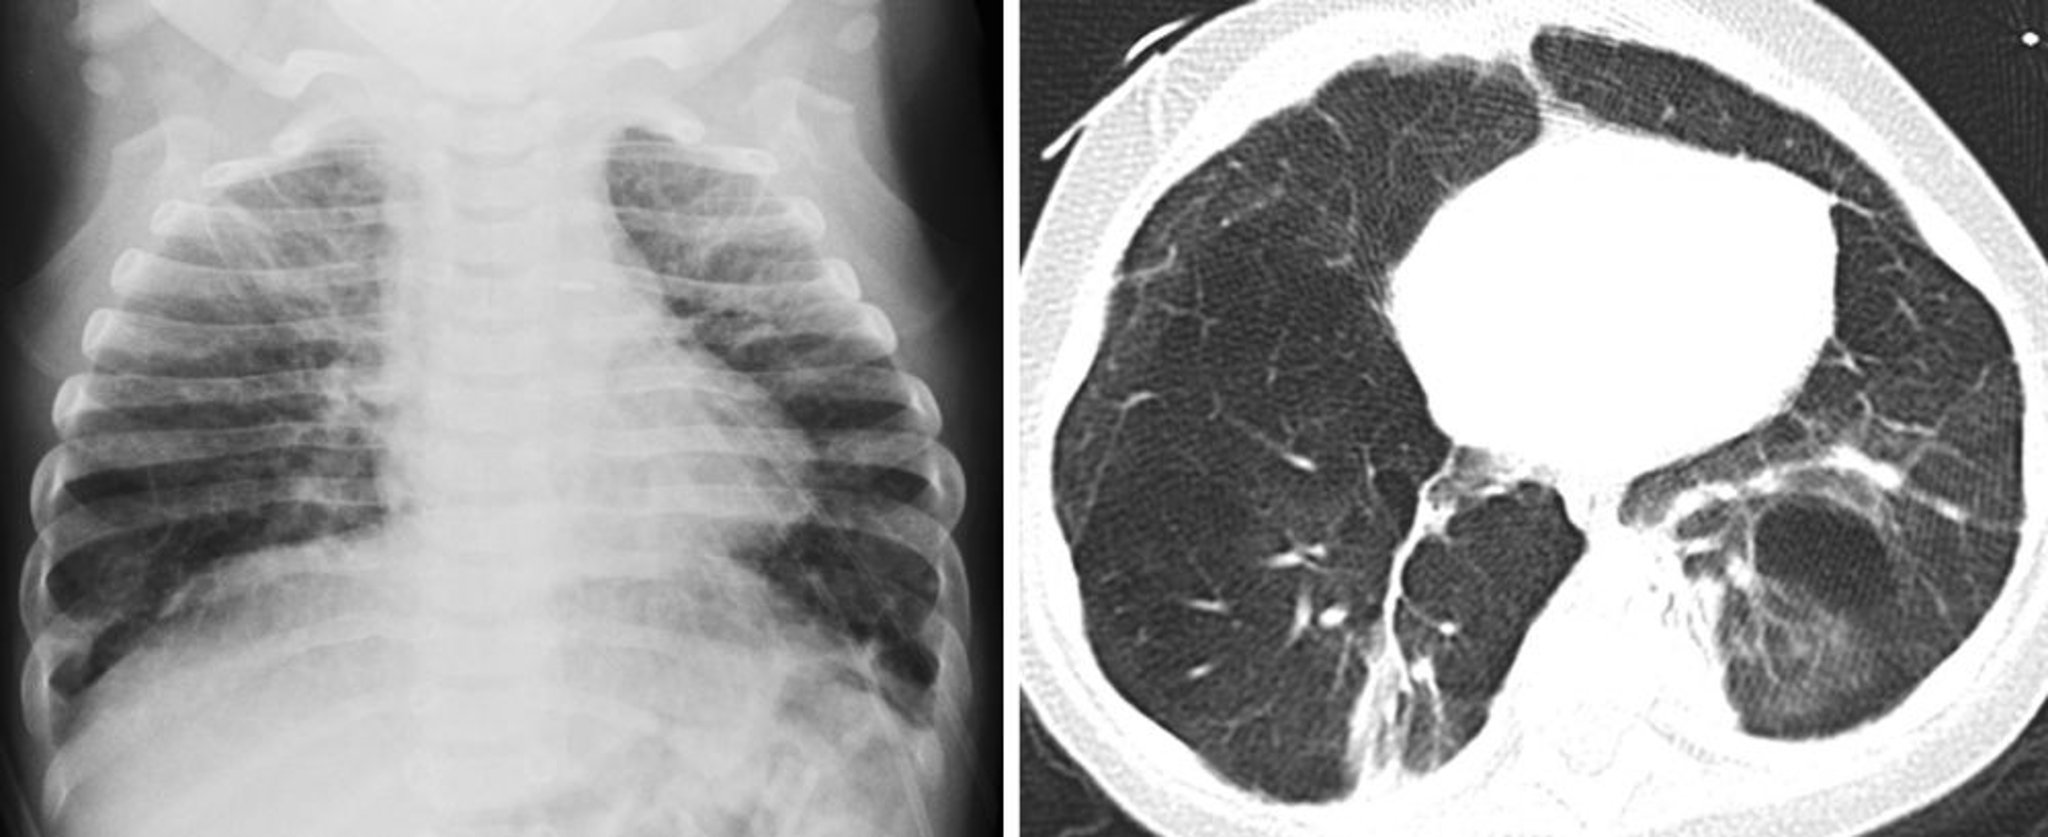

Бронхолегочная дисплазия (рентгенография и КТ)

Младенец на этих изображениях имеет в анамнезе недоношенность и бронхолегочную дисплазию. На рентгенографии грудной клетки слева показано грубое ретикулярное легочное затемнение и гиперинфляция обоих легких. На КТ-изображении справа визуализируются грубое ретикулярное затемнение легочной ткани и нарушение воздушности легкого, вызванные лежащими в основе альвеолярным перегородочным фиброзом и повышением воздушности паренхимы легкого.